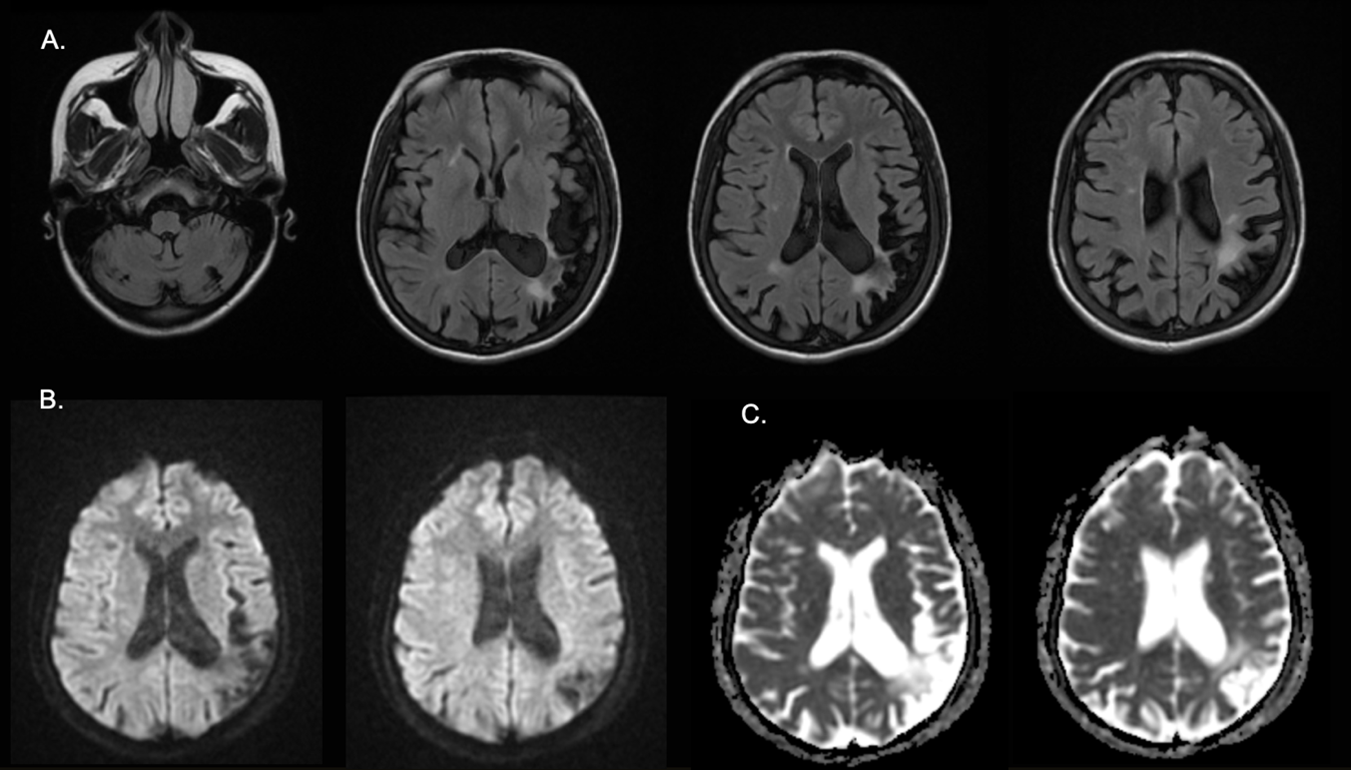

Se considero paciente con cefalea secundaria a trastorno vascular intracraneal, por lo que se realizó RMN cerebral simple + angiorresonancia evidenciando múltiples infartos antiguos, sin signos que sugirieran vasculitis o trombosis agudas arterial o venosa. (Figura 3)

Figura 3. Resonancia magnética cerebral- (A) FLAIR, ( B ) DWI, (C) ADC.